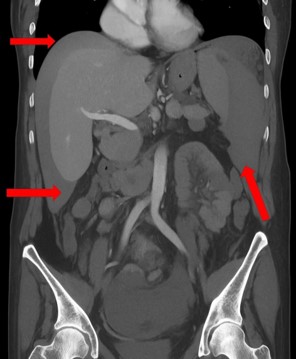

One day after the procedure, she visited the emergency department following three episodes of hematochezia and multiple episodes of near-syncope without loss of consciousness. She presented with intense abdominal discomfort, hypotension (BP=84/59 mmHg), and tachycardia (HR=110 bpm). A CT scan of the abdomen revealed a grade four splenic lesion in the middle third and free fluid in the splenic and perihepatic spaces (Figures 1 and 2).

Figure 2: Coronal computed tomography scan showing the presence of free fluid in the splenic and hepatic spaces.